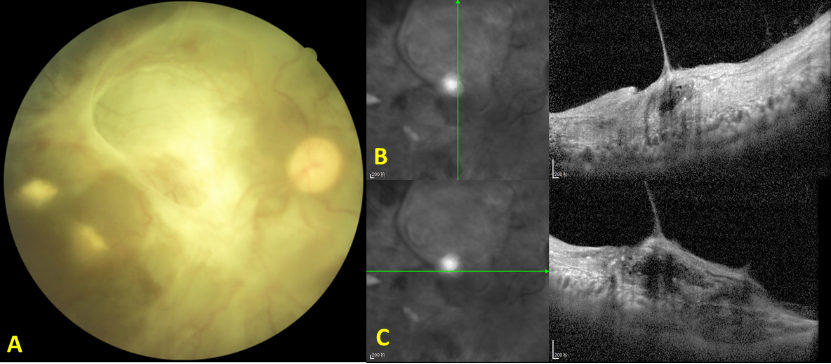

图1 病例1右眼眼底照相和OCT图

Figure 1 Fundus photograph and OCT image of the right eye of Case 1

(A)眼底照相显示视网膜增殖、纤维化;(B、C)OCT图显示视网膜全层结构不清、纤维化。

(A) Fundus photography reveals retinal proliferation and fibrosis. (B, C)OCT image demonstrates disruption of the full-thickness retinal architecture with fibrosis.